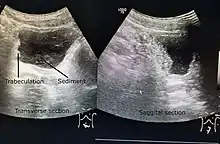

A paraplegic patient with neurogenic bladder on regular ultrasound follow-up showing thickened bladder wall with trabeculations and sediments within the bladder.

Ultrasound imaging can give information on the shape of the bladder, post-void residual volume, and evidence of kidney damage such as kidney size, thickness or ureteral dilation.[8] Trabeculated bladder on ultrasound indicates high risk of developing urinary tract abnormalities such as hydronephrosis and stones.[9] A voiding cystourethrography study uses contrast dye to obtain images of the bladder both when it is full and after urination which can show changes in bladder shape consistent with neurogenic bladder.[8]